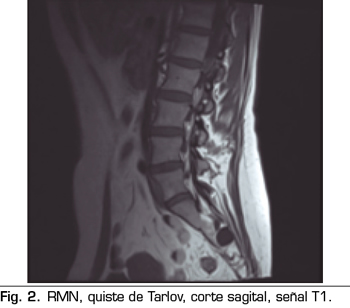

Una de las causas de dolor crónico a tener en cuenta son los “quistes perineurales” o “quistes de Tarlov”. Desde su primera descripción en 1938, son numerosos los artículos en los que se hace referencia. Se trata de lesiones nerviosas que se producen más frecuentemente en la zona sacra (8). En un estudio de Paulsen RD sobre la prevalencia y el drenaje de los quistes de Tarlov, se observó que en 500 pacientes que se sometían a una Resonancia Magnética (RMN) por dolor lumbar, el 5 % presentaba quistes de Tarlov y un 20 % de esos pacientes padecían síntomas relacionados con ellos (9,10). El diagnóstico suele ser casual mediante RMN; la cifra es variable debido a que solo se solicita a aquellos pacientes que presentan dolor lumbar crónico. Dicha técnica es más sensible que la tomografía axial computerizada (11,12).

Se realiza una RMN donde no se observan alteraciones estructurales que justifiquen las dolencias que presenta. Como hallazgo casual se describen quistes de Tarlov a nivel de S2. Se solicita una valoración por el servicio de neurocirugía, quienes dudan que la clínica sea consecuencia de los quistes (Figuras 1 y 2).

No obstante, debemos tener en cuenta las variaciones anatómicas como son los quistes de Tarlov, a expensas de las capas más internas de las meninges, la piamadre y el aracnoides. Estos quistes principalmente se sitúan en la zona sacra y lumbar, y suelen diagnosticarse de manera incidental en el transcurso de una RMN. Aunque la clínica producida por los mismos no es frecuente, se deben tener en cuenta como posible diagnóstico diferencial ante posible dolor lumbar crónico.